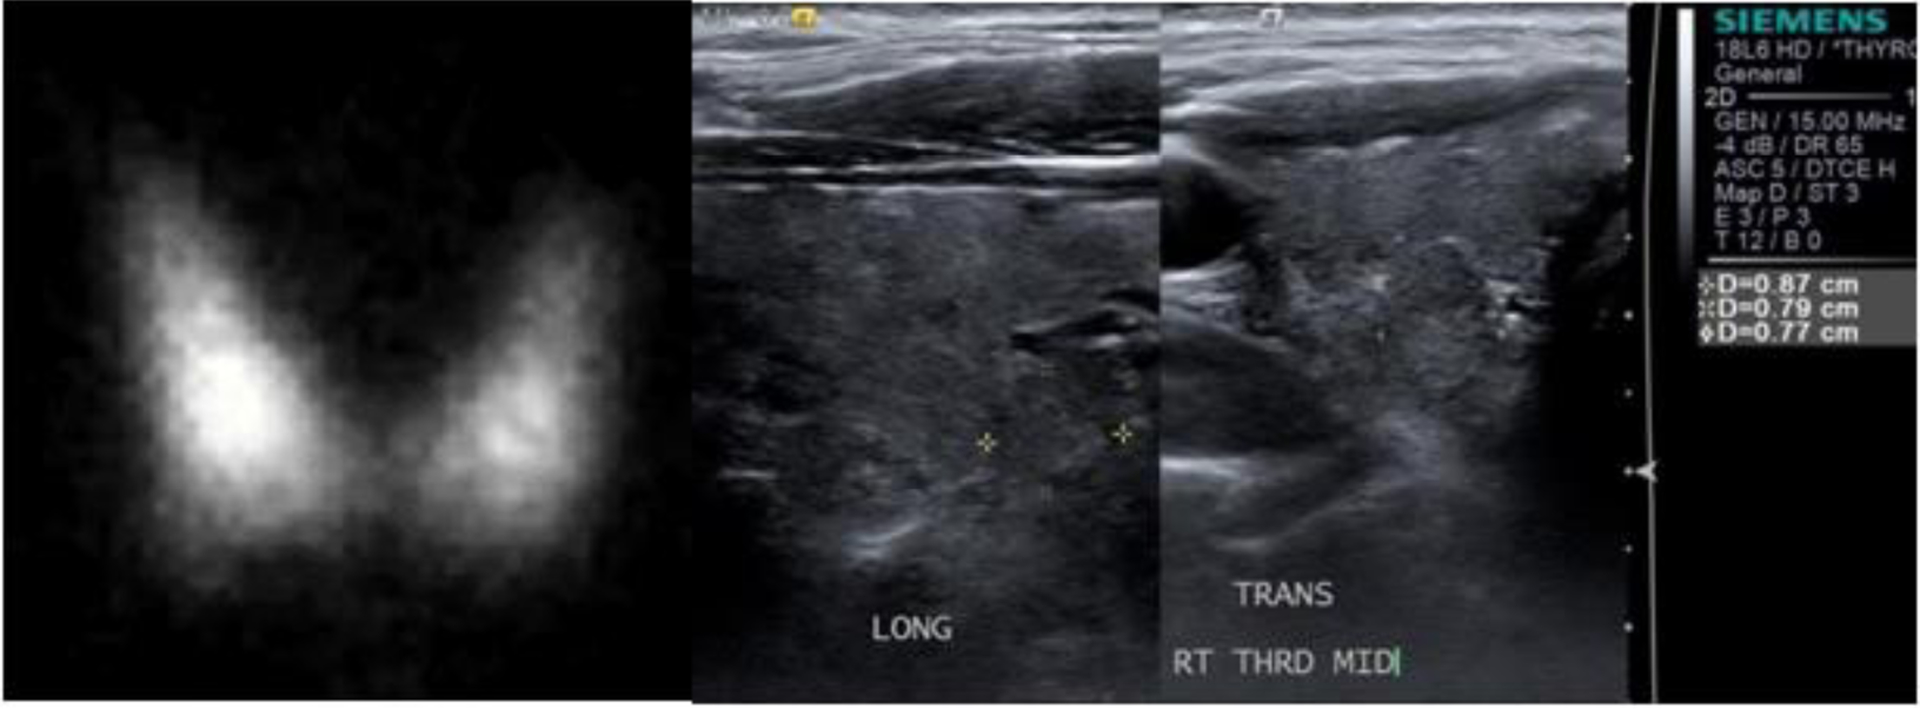

Abstract Image